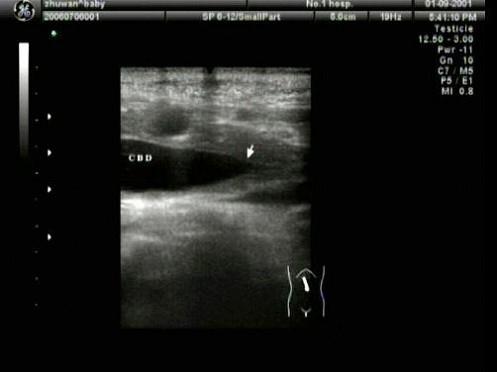

胆总管出现图中所示特点,称为?(?)A.双筒枪征B.海鸥征C.鸟嘴征D.鼠尾征E.平行管征

问题 胆总管出现图中所示特点,称为?(?)

选项 A.双筒枪征 B.海鸥征 C.鸟嘴征 D.鼠尾征 E.平行管征

答案 D